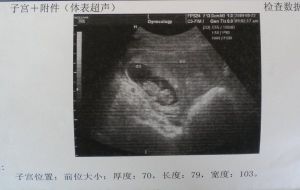

完全子宮縱隔B超檢查:據研究證明B超的子宮縱隔檢查的診斷較為準確。